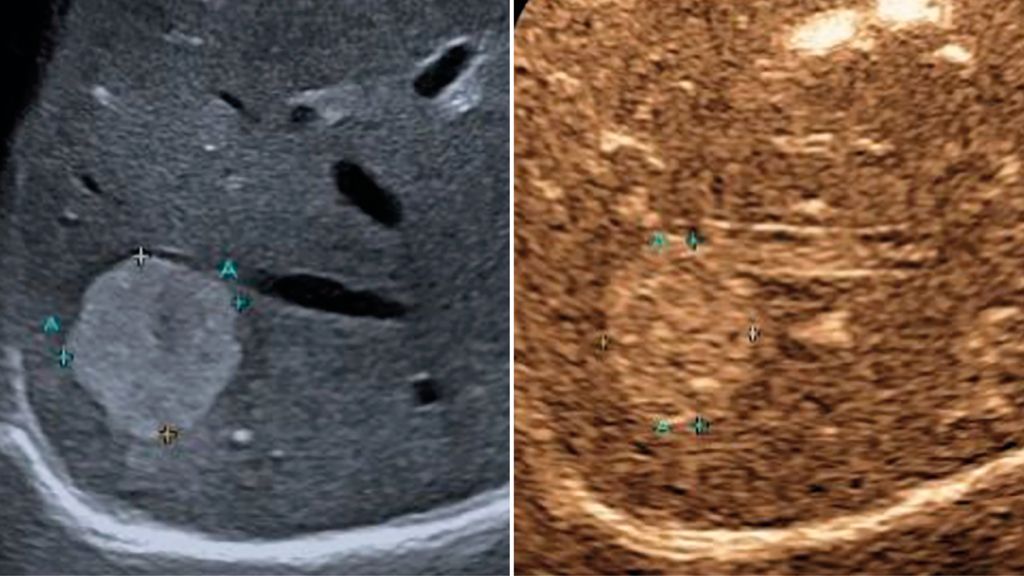

Trotz der hohen Aussagekraft moderner Ultraschallgeräte im B-Mode kann derzeit – mit Ausnahme des Screenings auf hepatozelluläre Karzinome bei chronischen Lebererkrankungen – kein generelles Leberscreening empfohlen werden.5 Die Mehrzahl fokaler Leberläsionen ist benigne, darunter fokale Steatosen, Zysten, Hämangiome oder fokale noduläre Hyperplasien (Abb.3). Maligne Raumforderungen sind in populationsbasierten Studien selten.6

Abb. 3: Darstellung einer fokalen nodulären Hyperplasie (FNH) in der arteriellen Frühphase nach Gabe von 1,2ml SonoVue® mittels CEUS (links) und in der mikrovaskulären Bildgebung (Canon®-superb «Microvascular imaging»-Modus), wo die Radspeichenstruktur besser zur Darstellung kommt